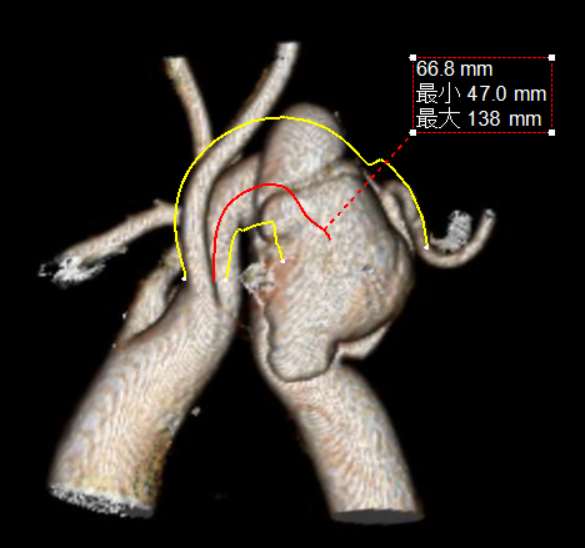

根据CT测量结果,预计锚定区位于LCCA后缘,瘤颈长度为22mm,弓部直径19-25mm。支架必须准确的锚定在LCCA后,如果释放时发生前跳,则会覆盖LCCA,受血管直径影响,重建LCCA的空间有限;如果发生后移,则会因锚定区不足产生I型内漏,补救成本巨大。

• 传统的CTAG支架从中间向两端打开主体,在释放支架时必须将Lunderquist导丝顶于大弯侧,才能减少支架移位的风险。

• 但在这个病例里,由于解剖结构异常的扭曲陡峭,导丝有可能无法完全支撑支架完全不移位。所以,保留支架在释放时的可控性非常的重要。如果可以使用GORE TAG可主动调控胸主动脉覆膜支架系统(CADS)由远端到近端的释放方式,提升支架的支撑稳定性,减少支架移位的可能。

解决方案:使用“壁咚” 技术,将CTAG支架锚定于LCCA后,必要时采取分段释放远端,提升锚定精准度。